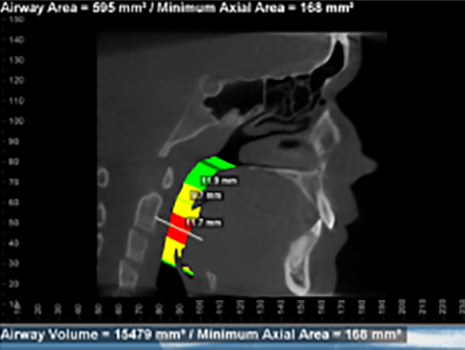

This before treatment airway shows a very constricted airway shown by the black.

The airway is black predominantly in the area behind the tongue. Having adequate room for the tongue in the mouth is critical for healthy breathing and sleeping.

The right photo shows an improved airway during treatment. There are no black zones. Most of the airway is yellow or green. The airway behind the tongue is the most constricted as shown by the red. As we continue treatment, we will allow more room for the tongue in the mouth and increase the airway.

These show the actual airway spaces. In this view it is easy to visualize the narrowing that happens behind the tongue. When the tongue does not have adequate room in the mouth, it will have a tendency to restrict airflow and lead to mouth breathing during the day, mouth breathing while exercising, disrupted sleep cycles, daytime fatigue, headaches, TMJ and ear issues, etc.